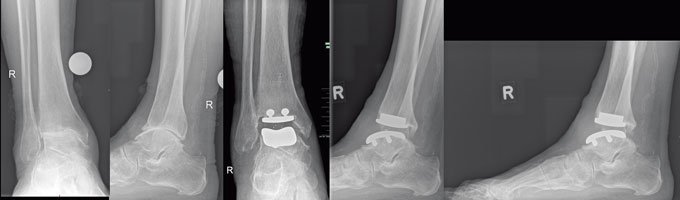

Oftmals hilft auch hier eine operative Korrektur, Arthrose vorzubeugen“, erklärt Dr. von Foerster. „Vor solch einer Operation schrecken viele Menschen erst einmal zurück“, weiß der erfahrene Mediziner aus seiner Sprechstunde. „Doch in der Hand eines erfahrenen Chirurgen, und hier ist die Anzahl der von ihm durchgeführten Gelenkersatzoperationen maßgeblich, sind die Aussichten auf Erfolg sehr gut.“ Häufig betrifft die Arthrose auch das obere Sprunggelenk. Entzündungszeichen am Gelenk sind typische Hinweise auf eine Arthrose im Sprunggelenk. „Heute ist es möglich, dieses Gelenk mit einer Endoprothese zu versorgen“, so Dr. von Foerster. „Auch diese Operationstechnik wird mit sehr gutem Erfolg durchgeführt.“ Die Ärzte der ENDO-Klinik Hamburg haben bislang mehr als 143.000 Kunstgelenke eingesetzt. Sie ist damit die führende Klinik in der Versorgung von Hüft-, Knie- und Schultergelenken und feiert in diesem Jahr ihr 40-jähriges Bestehen. Nach einem zweiwöchigen Krankenhausaufenthalt beginnt in der Regel dann ein physiotherapeutisches Training, damit die Muskeln wieder aufgebaut und der Umgang mit dem Kunstgelenk erlernt werden kann. Das neue Gelenk ist, je nach Beanspruchung, 20 Jahre oder länger haltbar. Danach kann es ohne Probleme ersetzt werden.